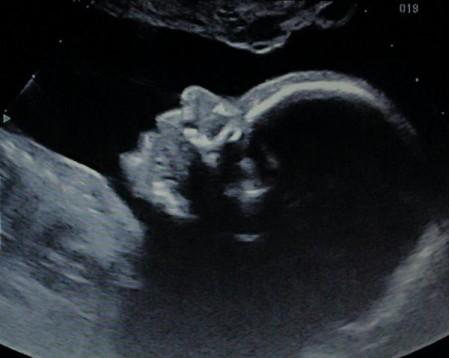

Lors de la première écho, il y a l'émotion de la rencontre, de la découverte de l'enfant à venir. Là, je ressens une joie immense en voyant son profil, puis son nez et sa bouche face à moi, en entendant battre son cœur... Cela fait quelques semaines maintenant que je le sens bouger, que je peux même le voir grâce aux ondulations de mon ventre. J'essayais d'imaginer où il en était de son évolution et là, je peux le voir, inconscient de l'examen qu'il passe. Mais c'est certain, nous le dérangeons. Cette sonde indiscrète qui vient sans la moindre hésitation se plaquer contre mon ventre, tentant d'être toujours plus près et cherchant le meilleur angle. Une sorte de distance s'installe peu à peu. Que se passe-t-il ?

À mesure que l'échographiste passe en revue les différentes parties du corps, les nomme pour nous et en prend les mensurations, je ne peux m'empêcher de guetter tout changement d'expression sur son visage. J'étais impatiente d'être à ce jour; les fêtes de fin d'année et les anniversaires qui s'y intercalent m'avaient juste permis de ne pas trop compter les jours... Mais j'avais oublié que cet examen est avant tout l'occasion de déceler d'éventuelles anomalies. Et voilà que je m'inquiète à chaque fois que l'échographiste examine un nouvel organe, une nouvelle partie du corps de mon bébé. Tant de mesures à prendre, des doigts à compter, des organes à vérifier, des os à mesurer... Tout y est, le compte est bon! Nous voilà rassurés; ou plutôt me voilà rassurée car je ne pense pas que mon cher et tendre ait un seul instant douté de la conformité de notre enfant !

C'est vrai qu'il est difficile de ne pas prendre la grossesse précédente en référence. D'ailleurs en voyant le profil de cet enfant se dessiner sur l'écran, je n'ai pu m'empêcher de dire à Rémi qu'il ressemblait à Ulysse. Ça l'a fait sourire. Mais maintenant que nous sommes à la maison, je vais chercher l'écho de Nils et Ulysse, celle de la 22ème semaine. Il n'y a qu'une mère pour penser une telle chose, le dire (le ridicule ne tue pas), puis tenter de le démontrer. Et je maintiens ! Pour l'instant, cet enfant à le même profil que son frère aîné (même si son père n'en est pas convaincu).